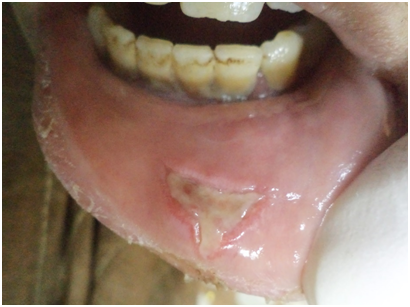

Oral ulcers, especially of the labial mucosa and tongue (Figure 1), were the commonest oral find in GBS while labial numbness, especially in the lower lip, enlarged major salivary glands, and xerotomia were very characteristic of SS. The commonest ocular manifestation in GBS, on the one hand, was intermittent uveitis whose severity ranged from mild to severe while cases of SS have presented typically xerophthalmia. No blindness was reported in the interval of the study as regards cases of GBS. Analogously, no cases of SS did run a transformation course into lymphoma or any other malignancy. Neuro-Behçet involvement and brain aneurysms in GBS, on the one hand, and the follow-up of SS cases, on the other hand, were assessed periodically by MRI. Normal images were obtained in the eighteen cases for this 3-year-old study (Table 1). Sonographically, superficial structures of the head and neck in GBS and SS were assessed. For cases of GBS, a single case has shown a subacute atherosclerosis in the carotid artery but no salient glandular changes were sonographically evident. However, cases of SS revealed a glandular parenchyma of heterogeneous echopattern. There were unmistakable bilaterlal diffuse miliary cystic cavities with patchy calcifications, spotting the underlying atrophic parenchyma. This has overtly promoted a “honeycomb” appearance on the sonograph. No other salient finding could be accentuated (Figure 2).

Figure 1 Recurrent ulceration of labial mucosa in BD.